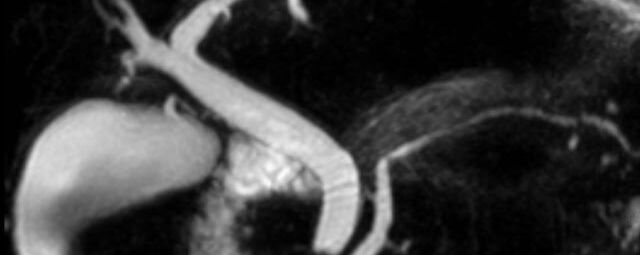

- kardiale Ischämiediagnostik mit medikamentöser Stress-MRT (Adenosin)

- Infarktnarbendarstellung/Vitalität

- Kardiomyopathien (z.B. Myokarditis, DCM, HCM/HOCM, Amyloidose, Sarkoidose)

- Klappenbeurteilung mit Phasenkontrastangiographie

- Tumoren Herz und Mediastinum

- Fehlbildungen

- MR-Angiographie zur Erfassung und Verlaufskontrolle von Aneurysmen der Aorta thorakalis und ihrer Gefäßabgänge